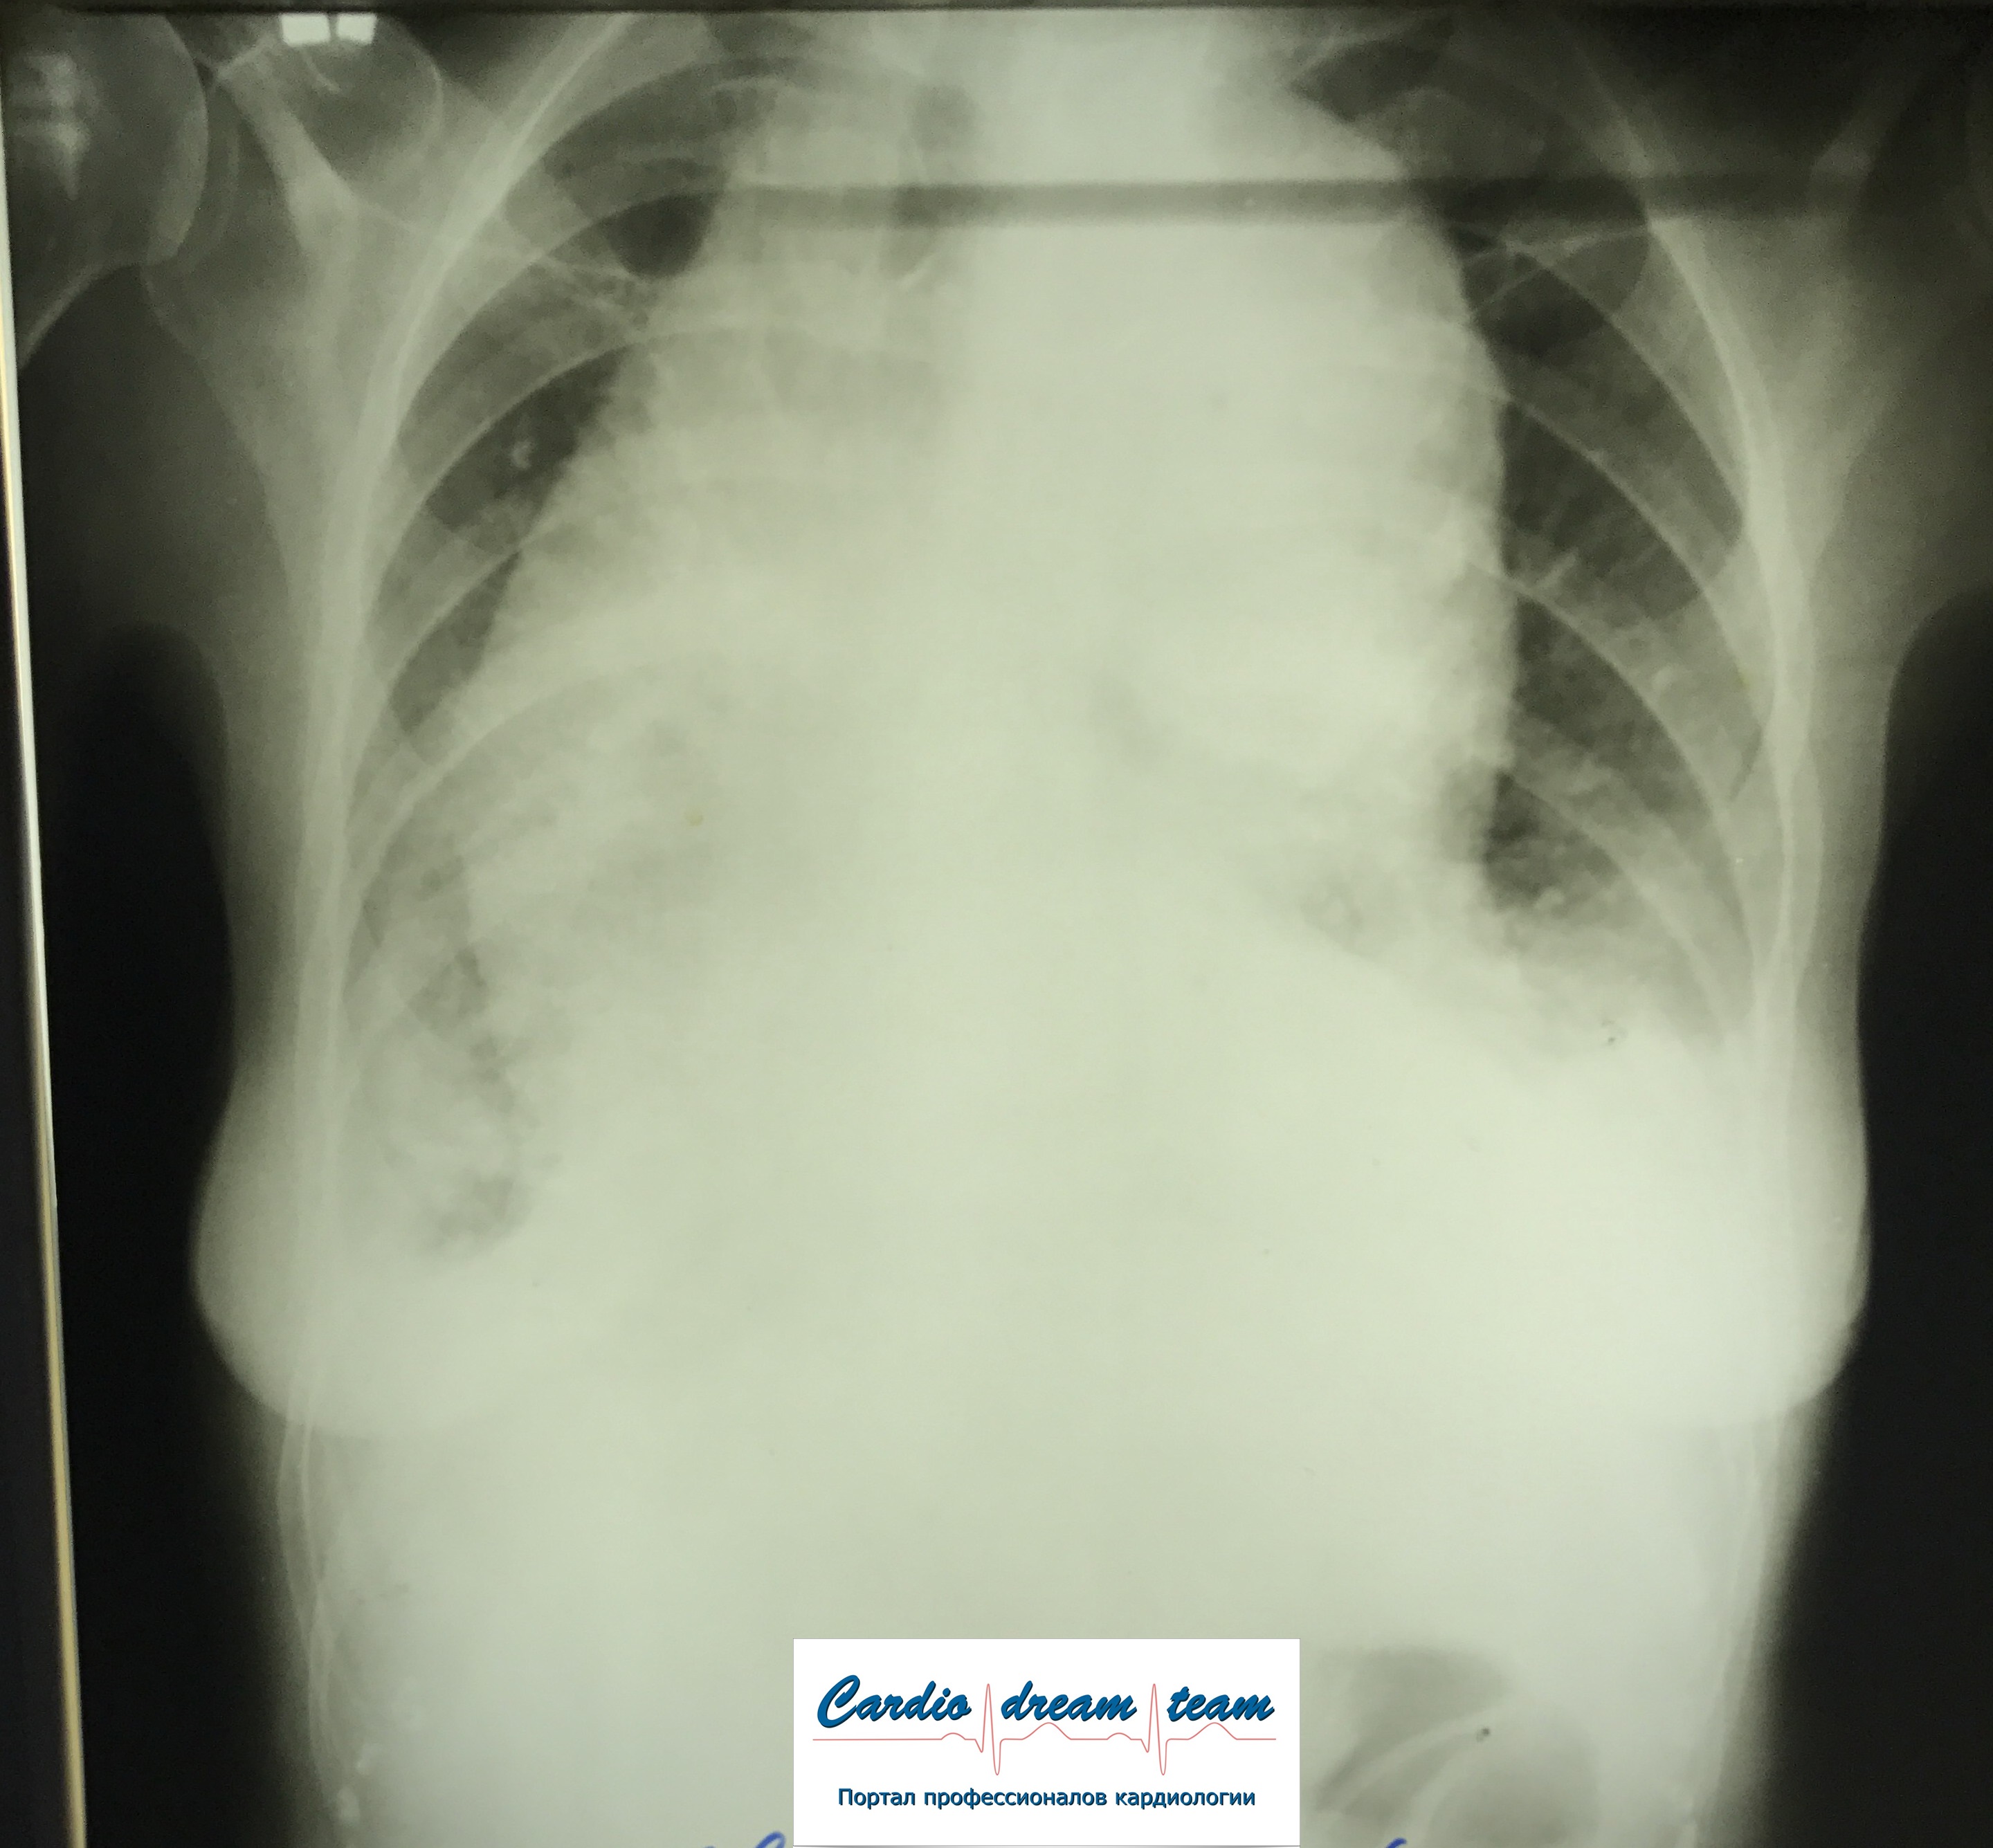

М, 69 лет. РАА. На первом снимке расширение срединной тени. На втором гемоторакс в результате прорыва крови из аорты в плевральную полость.